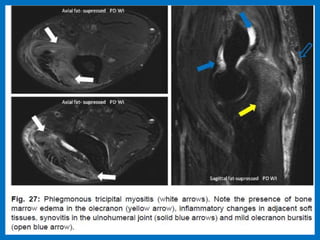

Avulsion of the distal triceps tendon (white arrow), with extensive overlying olecranon bursitis (black

arrows). There is cortical disruption (arrowhead) compatible with a small osseous avulsion.